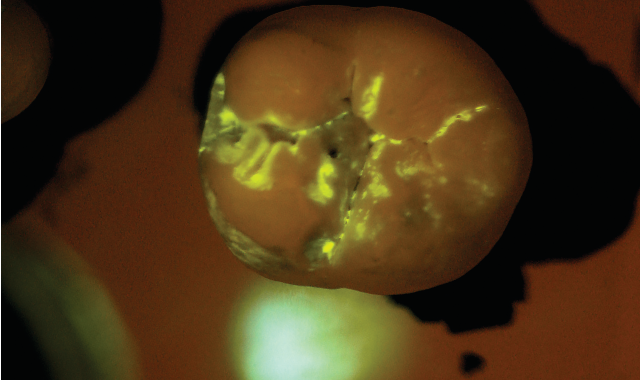

SB: The practice would administer the diagnostic test as part of a routine prophy exam. We have developed a mouth rinse where the targeted starch particles are dispersed at a low concentration in water. The patient rinses first with the diagnostic solution and then with plain water. All that remains after the water rinse are the particles that have penetrated

the tiny porosities in the enamel and attached themselves temporarily to the active subsurface lesions. The particles contain molecules that fluoresce or light up under exposure from a standard blue curing light. Within seconds, the dentist receives a direct visual diagnosis because the illuminated areas indicate areas of porosity.

After the patient drinks the mouth rinse containing the targeted starch particles and then rinses with water, particles adhering to enamel porosities fluoresce under a standard blue curing light.